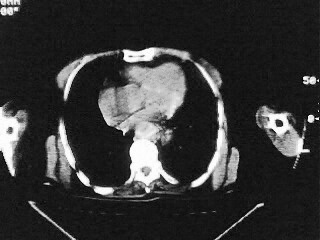

女,79,咳 嗽月余,无其它不适

(1)食管裂孔疝(2)贲门失弛缓症。建议行上消化道钡餐检查。

后纵隔内左心房至肝左叶后方椎体中线偏左巨大软组织包块,其壁均匀比较薄,其内可见宽气液平。

考虑食管裂孔疝。建议钡餐检查